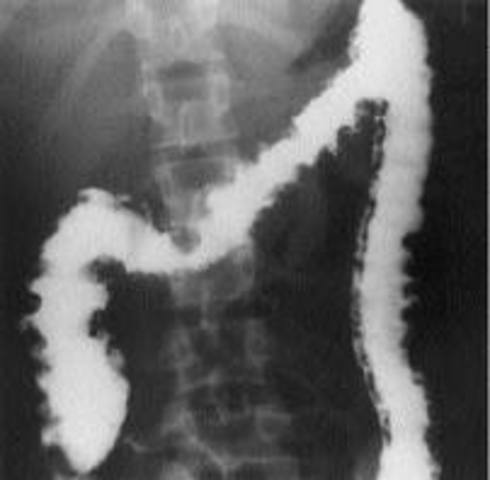

• Barium Enema

Barium Enema

By the age of 50 a person should get a barium Enema, also known as a lower gastrointestinal examination. In this test, the colon is filled with a contrast material containing barium, by pourig it into a tube inserted in the anus. The barium blocks x-rays, allowing it to show up easily, and abnormalities indicating colon cancer can be seen. It should be done every 5 years.